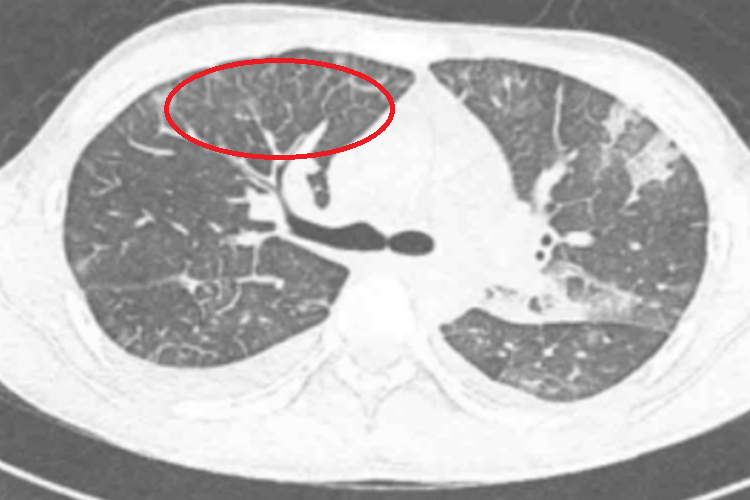

纯磨玻璃肺结节是指在胸部CT扫描中呈现的特定肺部结节形态,此结节在影像上表现为密度均匀一致、呈现云雾状的磨玻璃样改变,没有实质性的致密成分。

- 在CT影像上表现为肺部局部区域密度增高,但增高程度不足以掩盖其中的血管和支气管影,密度介于正常肺组织与实性结节之间,呈现出磨玻璃样的视觉效果。